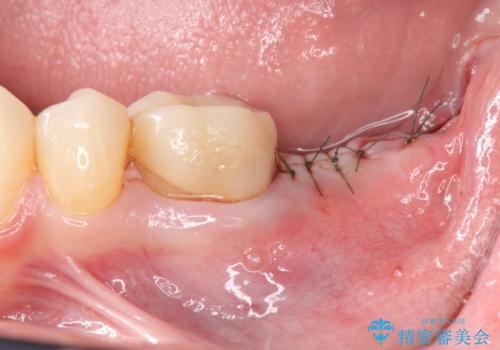

最後方臼歯のインプラント補綴

- 矯正治療・銀歯のやりかえ希望で来院されました。

矯正治療により歯並びの改善を行いつつ失われた最後方臼歯をインプラントを用いて咬合機能回復します。

- 40万円(ストローマンインプラント・カスタムチタンアバットメント・メタルボンドクラウン)費用は治療当時の料金となります

最後方臼歯を喪失した場合、入れ歯・インプラントによる咬合機能回復方法があります。

今回はしっかりと噛むことができ、取り外しの必要のないインプラントによる補綴を行いました。